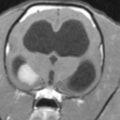

正常な脳室

拡張した脳室